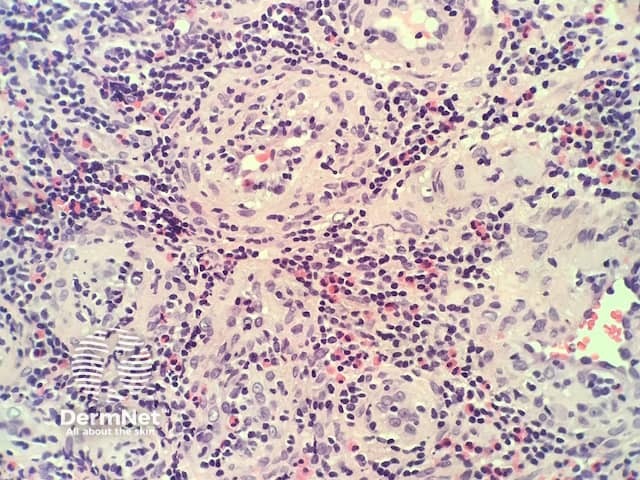

In epithelioid haemangioma, histopathologically there is a proliferation of blood vessels with epithelioid endothelial cells (figures 1,2). The endothelial cells are plump and have abundant eosinophilic cytoplasm sometimes resembling histiocytes (best seen in figure 2). As the endothelial cells are so plump, sometimes it is difficult to appreciate vascular spaces and the aggregates may resemble granulomas. Accompanying the vascular proliferation are collections of lymphocytes an numerous eosinophils (figures 1,2).

Figure 2